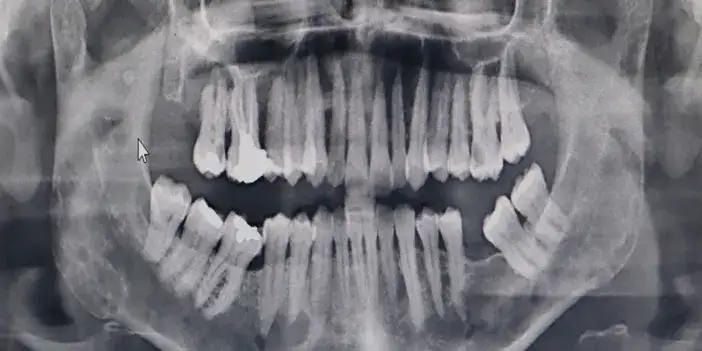

OMÜ Diş Hekimliği Fakültesi Dekanı Prof. Dr. Kaan Gündüz, vatandaşların ağız içi yaraları çoğu zaman önemsemediğini, tütün kullanımı, yetersiz ağız bakımı, güneş maruziyeti ve HPV virüsünün ağız kanserlerinin artışında etkili olduğunu ifade etti. Ağızda 2 haftadan uzun süren yaralar, sebepsiz diş sallanması, uyuşukluk ve çene ağrıları mutlaka dikkate alınması gerektiğini belirten Prof. Dr. Gündüz, ağız kanserinden korunma yolları arasında tütün ve alkol kullanımını azaltmak olduğunu belirtti. Prof. Dr. Gündüz, “Oral kanserler dediğimiz şey aslında başlangıçları çok hızlı ve sinsi gelişen durumlar. Bundan dolayı mutlaka hastaların 2 haftadan uzun süren ağızdaki yaraları eğer mevcutsa en yakın diş hekimlerine başvurmaları gerekmekte. En son yapılan, 2022 yılında Sağlık Bakanlığı yapmış oldu araştırmada 2 bin 246 tane ağız kanserine rastlanmış. Bu vakaların 551 tanesi ölümle sonuçlanmış. Bu da Türkiye kanser görülme olasılığını yüzde 1'ine tekabül ediyor ama şimdi şöyle bir durum var. Şimdi bizim insanlarımız kulağından bir damla kan gelince hemen işte gerekli doktora gider iken ağzından kan gelme durumunda çok fazla önemsemiyor. Yani ağız, dişler çok fazla önemsemiyor ne yazık ki. Ancak Özellikle son yıllarda artan tütün kullanımı ki bunun formasyonları var biliyorsunuz işte ne bileyim nargilesinden, piposundan, purosundan artmasından dolayı oral hijyenin, ağız bakımının eksikliğinden dolayı ve son yıllarda özellikle sizlerin de televizyonlarda veya işte bazı haber kanallarına duyduğunuz Human Papilloma Virüsü dediğimiz HPV'nin yaygınlaşmasından dolayı güneşe maruziyetinden dolayı insanlarda özellikle oral kanserler çok daha fazla sıklıkla görülüyor” diye konuştu.

Ağız kanserinde erken tanı gerçekleşirse hastaların ölümle sonuçlanmasının önüne geçilebileceğini ifade eden Prof. Dr. Gündüz, “Biz kurum olarak Karadeniz'in en büyük üniversitesiyiz ve de fakülte olarak da Karadeniz'de büyük bir hizmet vermekteyiz. Ortalama yaklaşık günde 500 hasta, aylıkta 10 bine yakın hasta bakıyoruz. Biz yapmış olduğumuz seminerlerde hem öğrencilerimizi hem asistanlarımızı hem de halkımızı bu konuda bilgilendirmeye çalışıyoruz. Erken tanı eğer gerçekleşirse bu hastalıkların ölümle sonuçlanmasının nispeten önüne geçmiş oluyoruz. Çünkü erken tanı biliyorsunuz her kanser vakasında çok önemli bir yer tutmakta. Herhangi birisi ağzında eğer 2 haftanın üzerine geçmeyen bir yara varsa mutlaka en yakın diş hekimine başvurması gerekmekte. Sebepsiz yere dişlerin sallanması, uyuşukluk olması, yüzde sebepsiz ağrıların, çene bölgesinde sebepsiz ağrıların oluşması kanserlerin başlangıç bulguları arasındadır. Zaten kanserlerin en fazla oluştuğu yerler ağız içerisinde dilin özellikle arka kenarlarıdır. Bunlar ne yazık ki başlangıçları da ağrısız olduğu için bir kısmının gözden kaçabilmekte. O yüzden insanlarımızdan, halkımızdan bu konuda dikkat etmeleri, eğer böyle bir lezyonla muhatap olurlarsa mesela bir yakınından ağız içerisindeki görüntüsünü çekmesini talep etmeli. 2 hafta sonra da aynı şekilde bu görüntü duruyorsa veya daha da büyümüşse en yakın merkeze gitmesini önermekteyiz” ifadelerini kullandı.